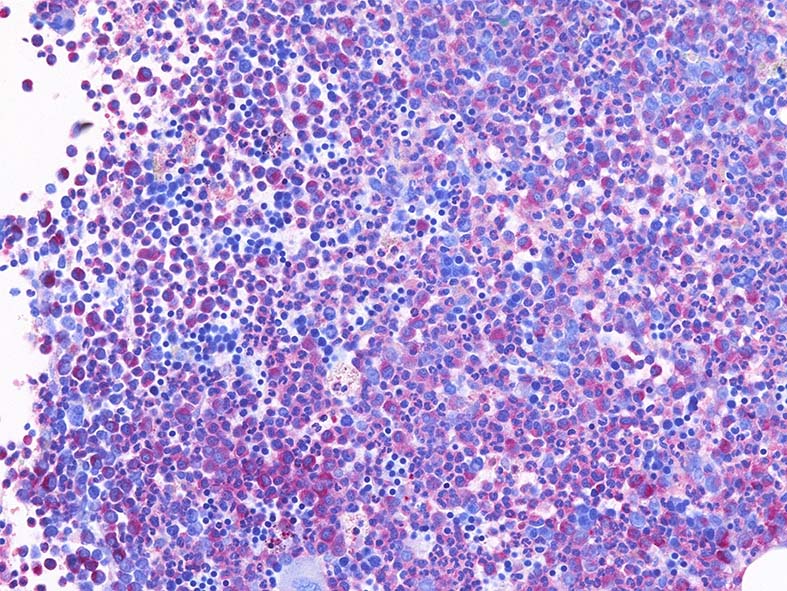

Naphtohl-ASD-CAE Fig.01

Fig.01: hypercellular marrow. ASDで赤染する細胞の増加=granulopoietic hyperplasiaがある.

Fig.02: 幼若な顆粒球が増加している. 赤芽球は散在しており血島は不明瞭である. 過形成髄なのにFig.02に成熟大型巨核球はみられない.